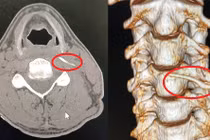

Sau đó, Junjun được đưa tới bệnh viện. Tại đây, các bác sĩ đã dùng nhíp nhẹ nhàng gắp xương cá của trẻ ra một cách chuyên nghiệp.

Theo các bác sĩ vị trí của xương cá khá lắt léo, hành động vỗ lưng để con ho làm bật xương cá ra của người bố là hoàn toàn đúng đắn. Nếu cho trẻ uống giấm hay uống nước sẽ không mang lại hiệu quả.